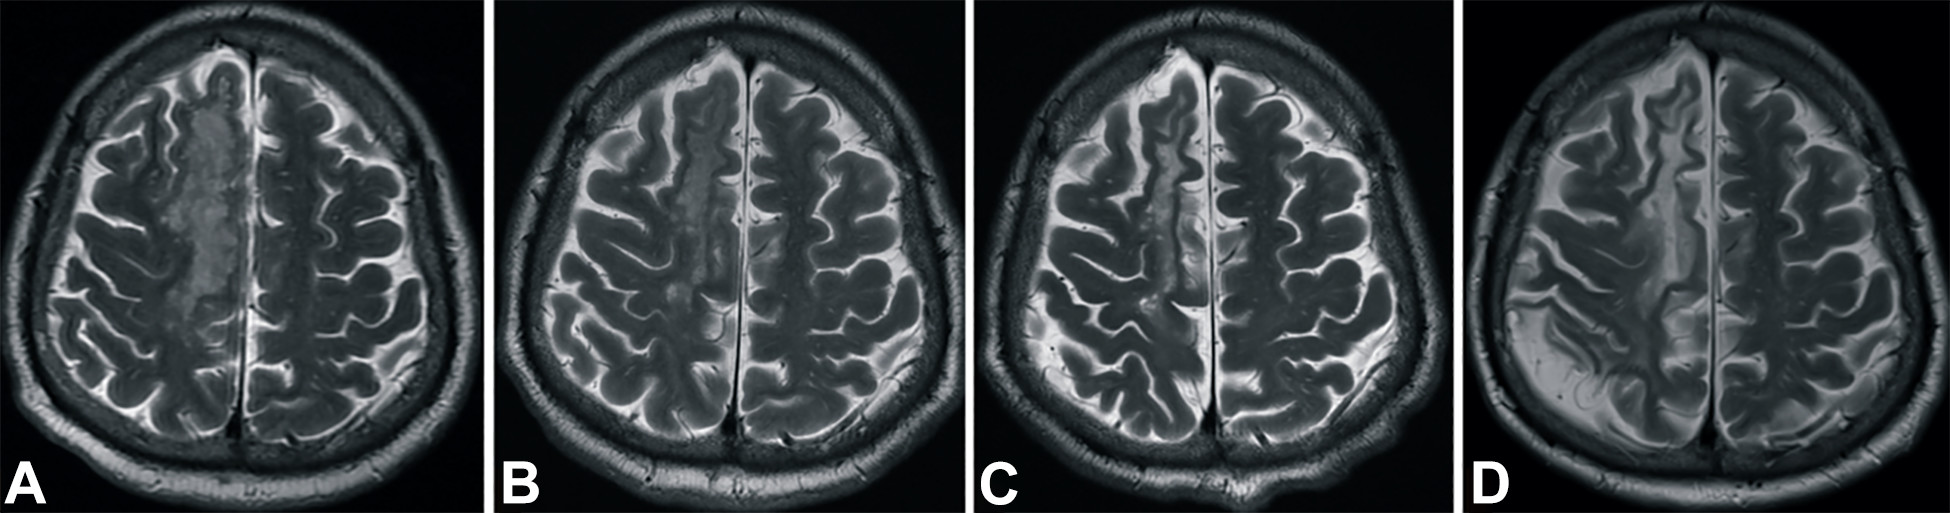

梗塞發(fā)生后2小時(shí)、8 天、3 個(gè)月和 6個(gè)月獲得的T2加權圖像顯示右側放射冠白色強度增加(圖3A-D)。

中風(fēng)后2小時(shí)和輸血后6個(gè)月獲得的T2加權圖像。

圖3.中風(fēng)后2小時(shí)和輸血后6個(gè)月獲得的T2加權圖像。(A)中風(fēng)后2小時(shí),(B) 輸血后1天,(C) 輸血后3個(gè)月,(D) 輸血后6個(gè)月